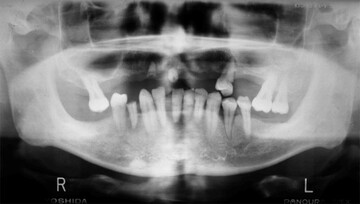

⑤レントゲン検査

・歯の状態

・骨の状態

・虫歯や歯石

・顎の状態など見えない所をチェックします

⑥かみ合わせの検査

レントゲンを見てもわかります

歯並びの影響で強く当たっている歯はどうしても歯周病が進みがち